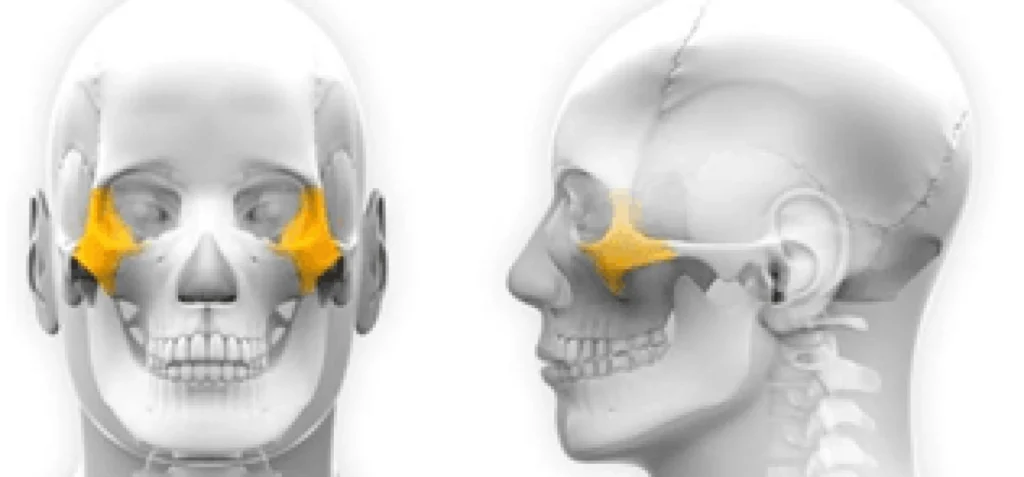

Les implants zygomatiques représentent une alternative innovante pour ceux qui sont mécontents de leur prothèse amovible. Mis au point dans les années 90 par le Dr Brånemark, ils affichent un taux de succès impressionnant, rivalisant avec les implants dentaires traditionnels. Leur double ancrage dans l’os zygomatique et l’os alvéolaire marque une différence cruciale, permettant une stabilité et une durabilité accrues.

Ancrage double de l’implant zygomatique :

Un implant zygomatique est plus long qu’un implant en titane classique. Il mesure de 3 à 5 cm. L’os des pommettes est d’excellente qualité, il ne se résorbe pas. Son volume osseux est généralement suffisant. Chaque pommette peut recevoir un ou deux implants. La partie de l’implant visée dans l’os zygomatique est rugueuse pour une meilleure accroche et cicatrisation osseuse, l’autre partie qui traverse le sinus et la muqueuse buccale est lisse pour éviter de fixer les bactéries. Le col de l’implant est angulé à 55 degrés pour rattraper l’axe d’insertion. Un pilier (violet) est vissé dans l’implant. Son épaisseur varie de 1 à 3 mm. Il est choisie en fonction de l’épaisseur de gencive. La prothèse se visse sur le pilier.